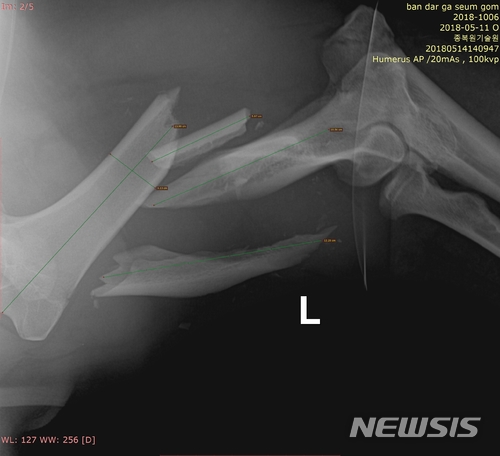

【세종=뉴시스】교통사고를 당한 반달가슴곰 KM53 복합골절 부위를 엑스레이로 촬영한 모습. 2018.05.18.(사진 = 국립공원관리공단 제공)[email protected]

KM53은 지난 11일 치료를 받기 위해 포획됐으며 17일 오후 1시부터 12시간에 걸쳐 왼쪽 앞다리 어깨부터 팔꿈치 사이 복합골절 부위 수술을 받았다.